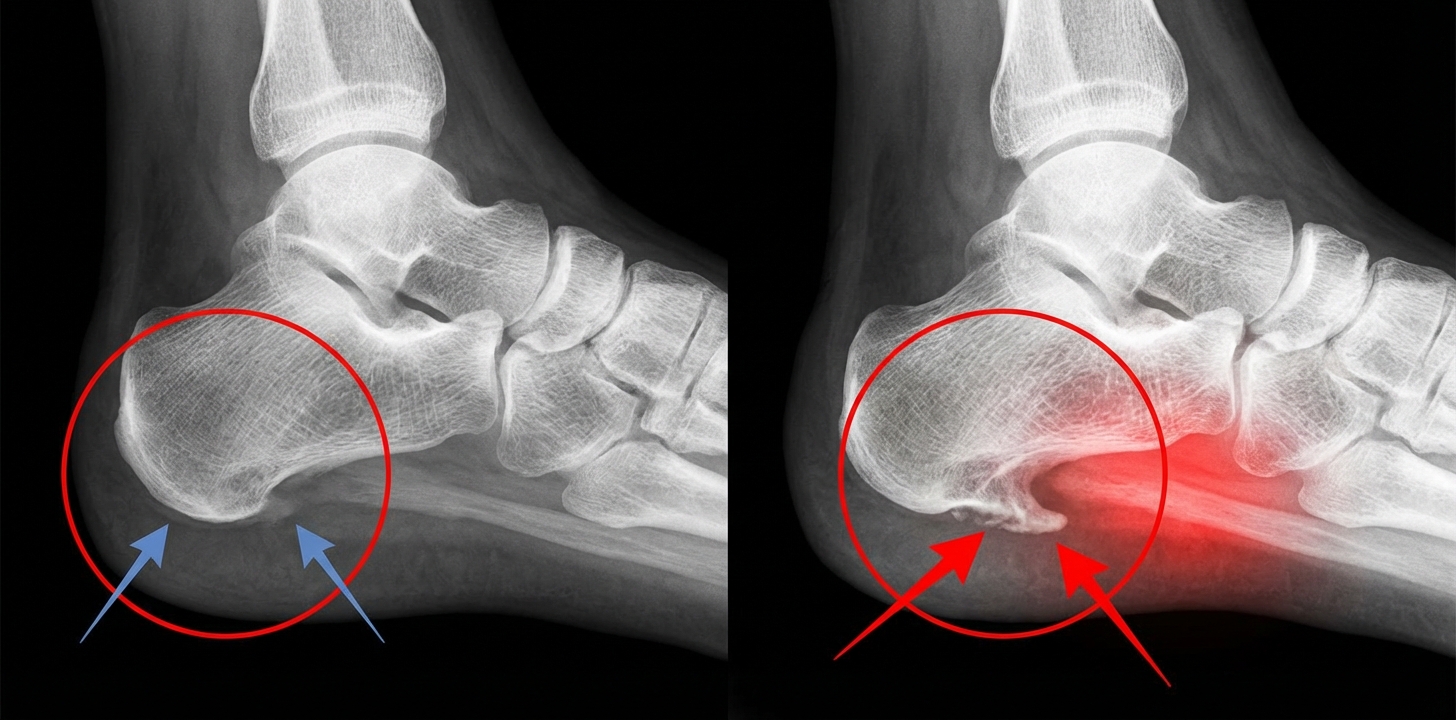

Rentgen, USG, test ciśnieniowy.

Diagnoza była jednoznaczna: ostroga piętowa i podrażnienie powięzi podeszwowej.

Organizm reaguje:

niewielkimi pęknięciami

zapaleniem

i w pewnym momencie ewentualnie wyrostkiem kostnym, znanym jako „ostroga”.

Wystarczy, że nacisk wielokrotnie uderza w niewielki punkt na pięcie.

Dopóki nic się nie zmieni, przy każdym kroku naciskasz na miejsce, które i tak jest już w stanie zapalnym.

Nic dziwnego, że to boli.